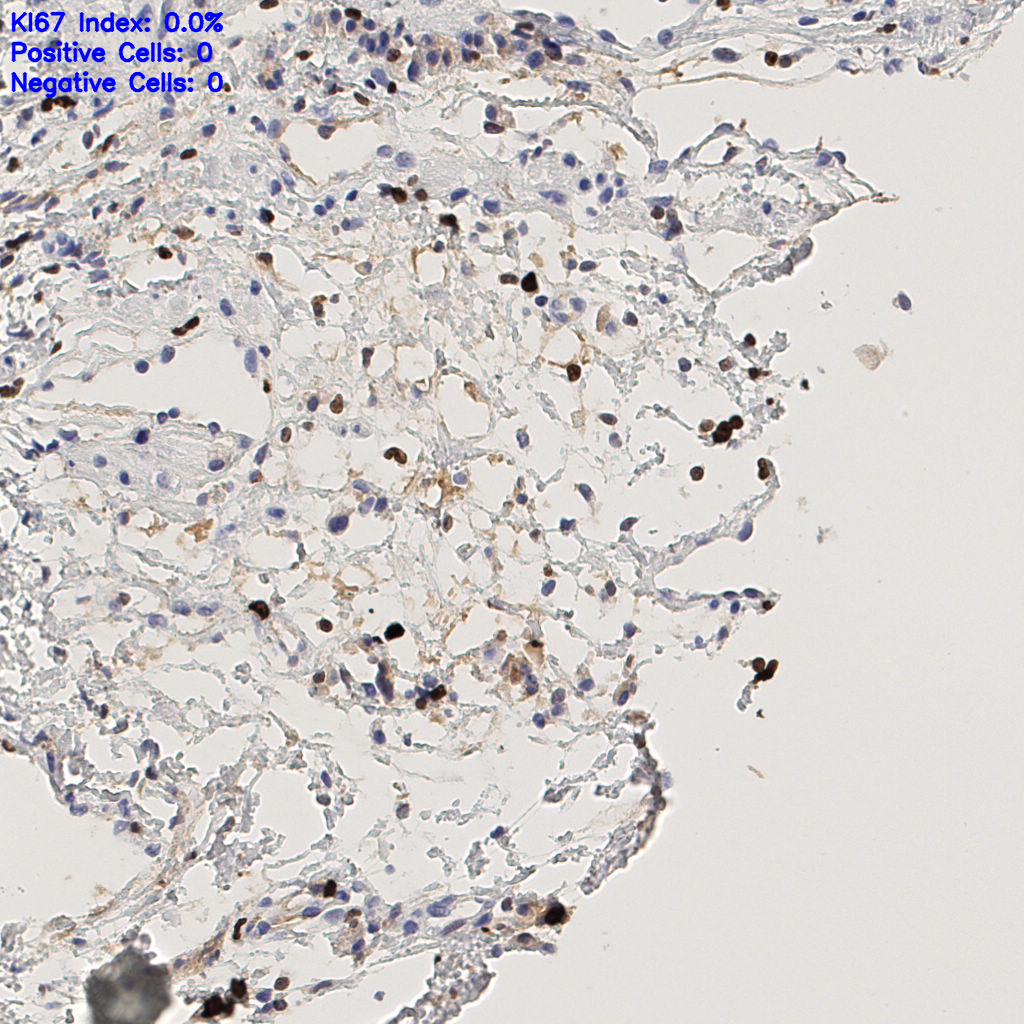

7.85%

Ki67 指数

阴 1104 阳 94

H255858-KI-67.ndpi

slice_44_6_x39424_y5376.png

slice_44_6_x39424...